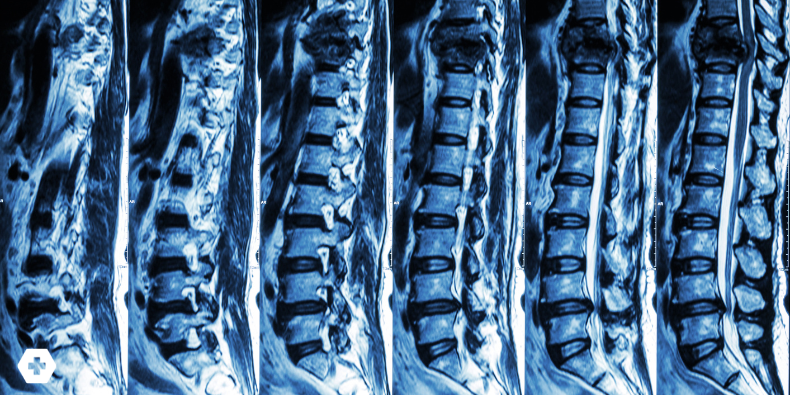

The thoracolumbar junction, especially T12–L1, is the most common site. Its position between the rigid thoracic spine and the more mobile lumbar spine makes it prone to stress during movement. When pain is present, it tends to be localized, worsens with standing or walking, and improves with rest.

For most suspected cases, plain AP and lateral spine radiographs are the best first step. Look for vertebral height loss or endplate deformities. If red flags are present, or you suspect retropulsion or other complications, escalate to CT or MRI—and refer urgently if needed.